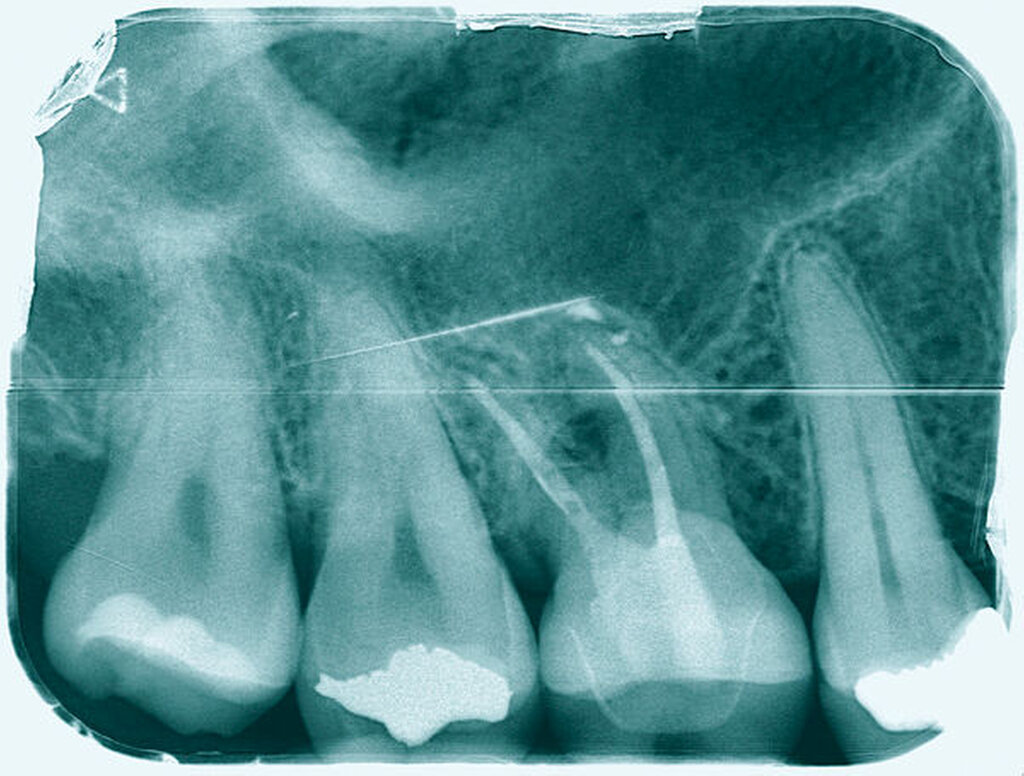

Eine 53-jährige Patientin stellte sich 2015 mit plötzlich aufgetretenen, starken Beschwerden an Zahn 16 und der Bitte um Abklärung vor. Es erfolgte die klinische und röntgenologische Befundung des Zahnes, der neben einer apikalen Parodontitis auch eine große, fast bis in die Furkation reichende Kronenrandkaries an der mesiobukkalen Wurzel aufwies. Um diesen vorhersagbar versorgen zu können, wurde der Patientin die endodontische Behandlung mit Amputation der mesiobukkalen Wurzel und anschließender Versorgung mittels Vollkrone als Alternative zur Extraktion aufgezeigt. Sie entschied sich für den Zahnerhalt.

So folgte nach der Wurzelfüllung die Amputation der mesiobukkalen Wurzel. Der Zahn wurde nach der Amputation auf Wunsch der Patientin zunächst mit einem Langzeitprovisorium versorgt, das im Verlauf gegen eine definitive Versorgung ausgewechselt wurde. Die Patientin ist seitdem an 16 beschwerdefrei, der Zahn ist stabil und hat eine gute Langzeitprognose.